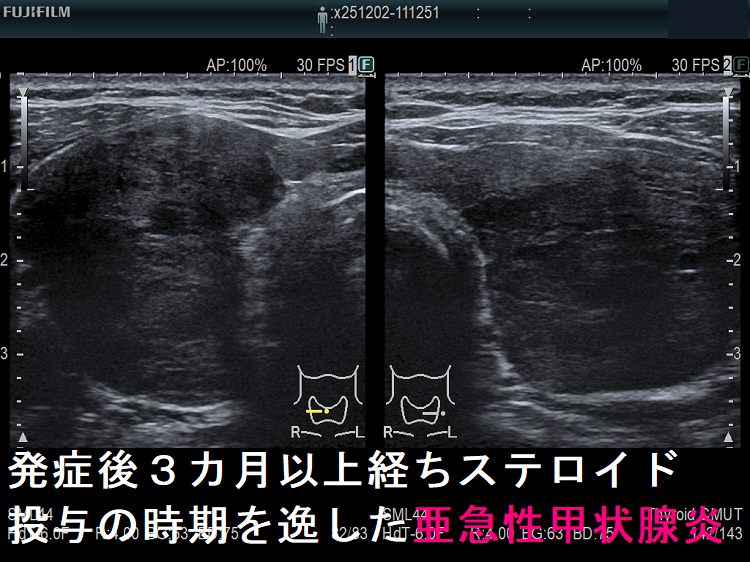

- 発症後数か月以上経ち、ステロイド投与の時期を逸した場合